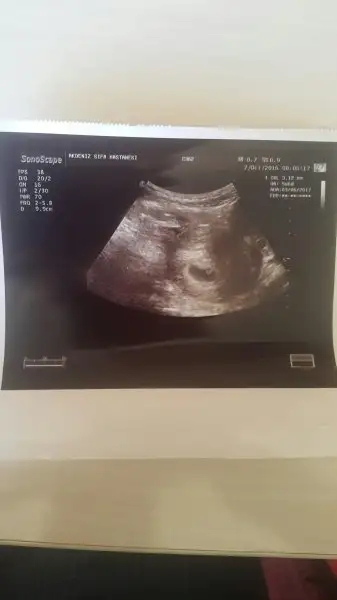

Şifa hastanesine gittim. Doktor pek bir surarsızdi ama zaten ama sadece bebegi görmek olduğu için bu duruma pek takilmadım. Nitekimde bebeği gördük. Kalp atışı icin haftaya bakalım dedi ama tabi ki bu suratsız adama gitmeyeceğim bir daha. Bütün enerjimi aldı sabah sabah. Ama çok şükür gördüm o minicik bebegimı. Bu boş gebelik değil dedi . Rahimime çevresinde kanama yok dedi. Her hangi bir sorun yok korkmana da gerek yok dedi. Sadece kalp atışlarını duymamış gerekiyor dedi onu da duyarız herhalde diyorum. 6+0 günlük çıktı bu ultrasonda bebek yani benim tahminime göre 3 gün geri de. Gerçi ben zaten hatırlamıyorum ne zaman regli olduğumu da. Bakalım haftaya neler olacak. Hepinize çok çok teşekkür ederim iyiki varsınız. Aşağıdaki de benim minik bebeğim ❤❤

• 2016-10-07 11.15.23.webp

2016-10-07 11.15.23.webp

6,5 KB · Görüntüleme: 82